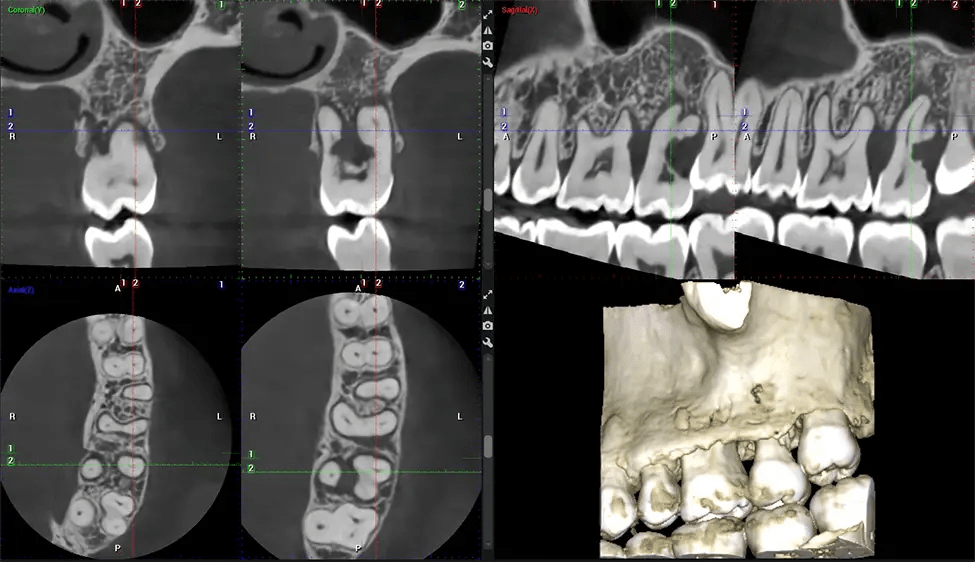

This 3D scan, called cone beam computed tomography, gives your dentist a more complete image of your oral anatomy and disease processes than a traditional X-ray. Unlike conventional X-rays, which capture a 2D image of your mouth from various angles, a 3D scan takes multiple digital X-rays for one image. It provides a complete view of your jaw, teeth, nerves, and soft tissues. This enhanced view allows dentists to detect minor issues not visible in traditional 2D scans, such as impacted wisdom teeth or bone fractures in the sinus cavity.

There are many benefits to using CBCT technology, especially compared to the traditional 2D X-ray format. One of the most significant advantages of CBCT scans is that they provide much more information than traditional X-rays. A scan lets your dentist see images from all angles of your jaw and mouth, including your sinuses, nasal cavity, cheekbones, and other surrounding areas. This added information helps your dentist craft a comprehensive treatment plan that addresses all aspects of your oral health.

Another significant benefit is that 3D imaging provides more precise images of your bone structure. These images are more detailed, providing you with a more accurate diagnosis. An accurate diagnosis means better treatment for you.

After the scanning process, the captured X-ray images are processed by the CBCT software, which applies algorithms to reconstruct a detailed 3D image of the scanned area. The software compiles these individual X-ray images and creates a digital 3D representation of the patient’s anatomy. The reconstructed 3D CBCT image can be viewed and analyzed by the dentist or radiologist. This image can be manipulated, rotated, and zoomed in or out to examine specific structures and evaluate the patient’s condition.

Our patented SCARA technology enables doctors to capture True Extraoral Bitewings that are as accurate at detecting caries as a 2D bitewing series, but with half the radiation dose. With our bitewings, doctors can view the apices of teeth on both jaws providing a more comprehensive view of the patients’ anatomy.

Planmeca 3D systems come with Autofocus, a technology that produces incredibly clear panoramic images, even on the interiors. This technology sets our 2D images apart from the competition.